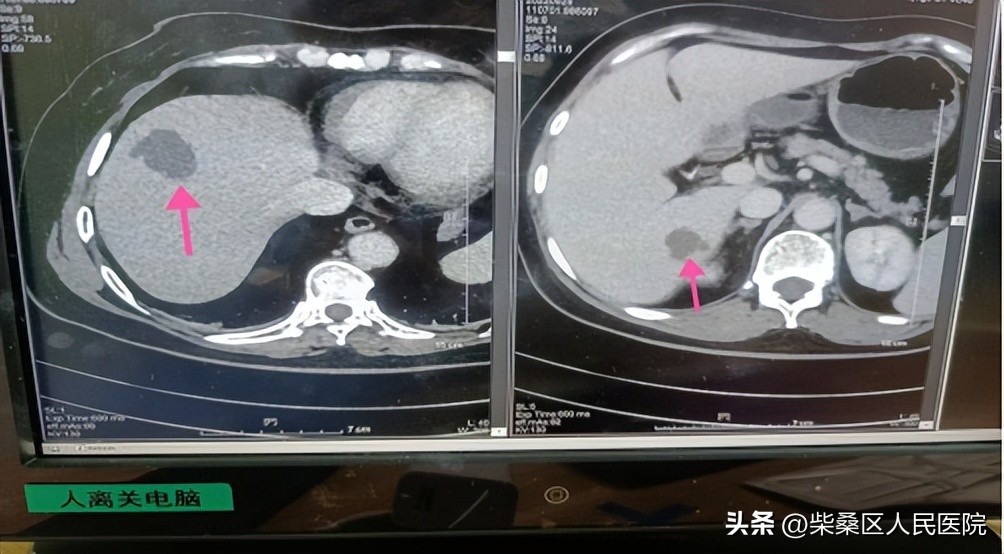

今年60岁的患者李女士,因发热伴腰腹不适来肝胆外科就诊,完善检查发现其血糖高,同时肝内有多处不规则脓肿。CT提示脓肿靠近肺及位置较深,如穿刺针刺入体腔抽取分泌物的话风险较大,不建议通过穿刺引流。考虑患者各项检查指标,判断其肝内多发脓肿应是由胆道感染和糖尿病引起的。

经肝胆外科负责人龚清组织科室讨论,决定采用抗感染+口服中药+降血糖的中西医结合方案,根据病情变化及时采用个性化治疗措施。患者经抗感染+口服自拟排脓解毒方1天后体温下降、3天体温恢复正常,连续治疗3周后复查彩超脓肿较前明显减小予以出院,嘱其继续口服中药1月复查彩超提示脓肿完全吸收。